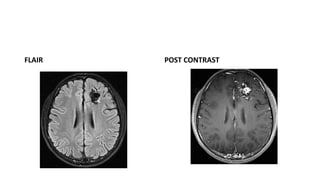

MRI

• MR findings

• T1WI

Tightly packed mass, “honeycomb” of flow voids Signal varies with flow rate, presence/age of

hemorrhage

• T2WI

Tangle of serpiginous, ‘honeycomb’ of flow voids . Little/no brain inside nidus. Some gliotic

high signal may be present

• FLAIR

Flow voids with surrounding high signal (gliosis)

• T2*GRE

Blooming if haemorrhage

• Post Contrast T1

Strong enhancement of nidus, draining veins

• Rapid flow may not enhance arteries, and seen as flow voids

• MRA

Helpful for gross depiction of flow Does note depict detailed angioarchitecture

FLAIR POST CONTRAST

• #26 FLAUR ;-Flow voids with surrounding high signal (gliosis) POST CONTRAST SHOWING Strong enhancement of nidus, draining veins